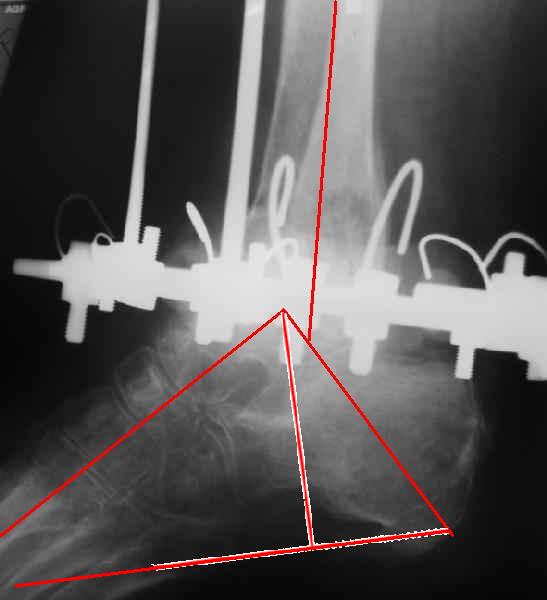

В самом деле, снимки некачественные - таран в ротации. Но даже по ним видно, что установка стопы минимум 104 градуса. С одной стороны - В Илизаровской технике пишут, что для женщин допустимо и 110. С другой - почему-то в цивилизованном мире настаивают на четких 90.

А если еще лучше присмотреться, таран в переднем подвывихе, что не кажется допустимым.